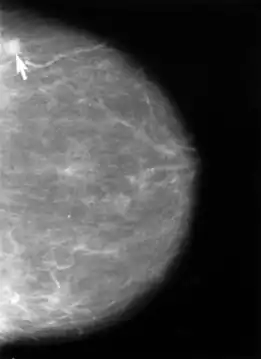

В настоящее время в мире в подавляющем большинстве случаев для диагностики рака женской молочной железы (РМЖ) используют рентгеновскую проекционную маммографию, пленочную (аналоговую) или цифровую. В Европе и странах Северной Америки цифровая маммография на основе детекторов прямого преобразования постепенно вытесняет плёночную из-за наличия больших возможностей по работе с полученным изображением и возможности интеграции с медицинской информационной сетью. Причём в рутинной цифровой рентгенографии применяются детекторы на основе a-Si (аморфного кремния), а в цифровой маммографии детекторы на основе a-Se (аморфного селена) вследствие прямого преобразования сигнала и отсутствия промежуточных этапов в получении рентгеновского изображения у селеновых детекторов. Самыми первыми и самыми старыми аппаратами (с 2000 года) на рынке являются маммографы General Electric (детекторы aSi с разрешением 4 пары линий на мм).

Следует отметить, что согласно рекомендации ВОЗ достаточным для диагностики РМЖ на ранних стадиях является аппарат, позволяющий получать изображение, с разрешением не менее 20 пар линий на миллиметр, для аналоговых, и 20 пикселей на мм², для цифровых установок. Аппараты с меньшим разрешением для ранней диагностики образований молочной железы не пригодны.

Рентгеновская маммография является золотым стандартом для выявления рака молочной железы, так как обладает самой высокой специфичностью (более 92 %). В развитых странах Европы все женщины старше 45 лет проходят обязательную процедуру рентгеновской маммографии, что позволило значительно снизить смертность от рака молочной железы. В России обязательным является регулярное обследование женщин старше 40 лет.